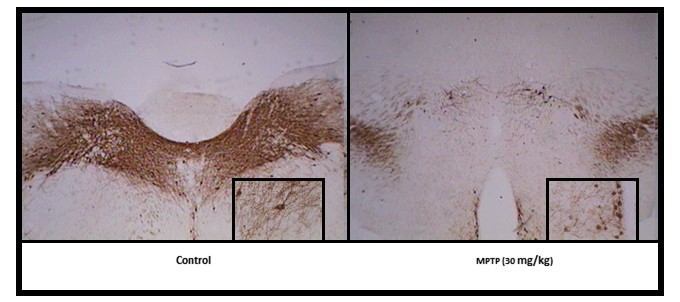

También hay una gran variabilidad en la sensibilidad al tratamiento con MPTP, lo que depende de la cepa de ratón intoxicada. La cepa C57Bl/6 es la más sensible a la intoxicación sistémica por MPTP, ya que en esta alcanza el sistema nigroestriatal de manera mucho más selectiva que en otras cepas murinas49 Esta variabilidad en la sensibilidad al MPTP se atribuye a diferencias genéticas.50 De los numerosos estudios con MPTP en ratones como modelo experimental de la EP, algunos se han basado en la administración subcutánea o intraperitoneal de una dosis de 10-20 mg/kg de MPTP en un intento de crear un modelo presintomático para el estudio de los mecanismos compensatorios que suceden a la intoxicación.50 Sin embargo, los dos modelos más utilizados en la actualidad son los denominados agudo y crónico por inyección intraperitoneal. En el modelo agudo se administran cuatro dosis de MPTP (20 mg/kg) en el mismo día y el animal se sacrifica al cabo de siete días.51,52 En el modelo crónico, podemos diferenciar dos pautas: i) administración de una sola dosis diaria de MPTP (30 mg/kg) durante cinco días consecutivos y sacrificio del animal a los siete días53,54 (Figura 3), y ii) administración de una dosis al día de MPTP (4 mg/kg) durante 20 días y sacrificio siete días después de la última inyección.55,56

Figura 3. Efecto de la administración intraperitoneal de MPTP en ratones de la cepa C57Bl/6. En el grupo control se observa una mayor inmunorreactividad a Tirosina Hidroxilasa en Sustancia Nigra, lo que se traduce como una mayor densidad de neuronas dopaminérgicas en comparación con el que recibió 30mg/Kg de MPTP por 5 días, en el que la inmunorreactividad disminuye cuantitativamente más del 70%.